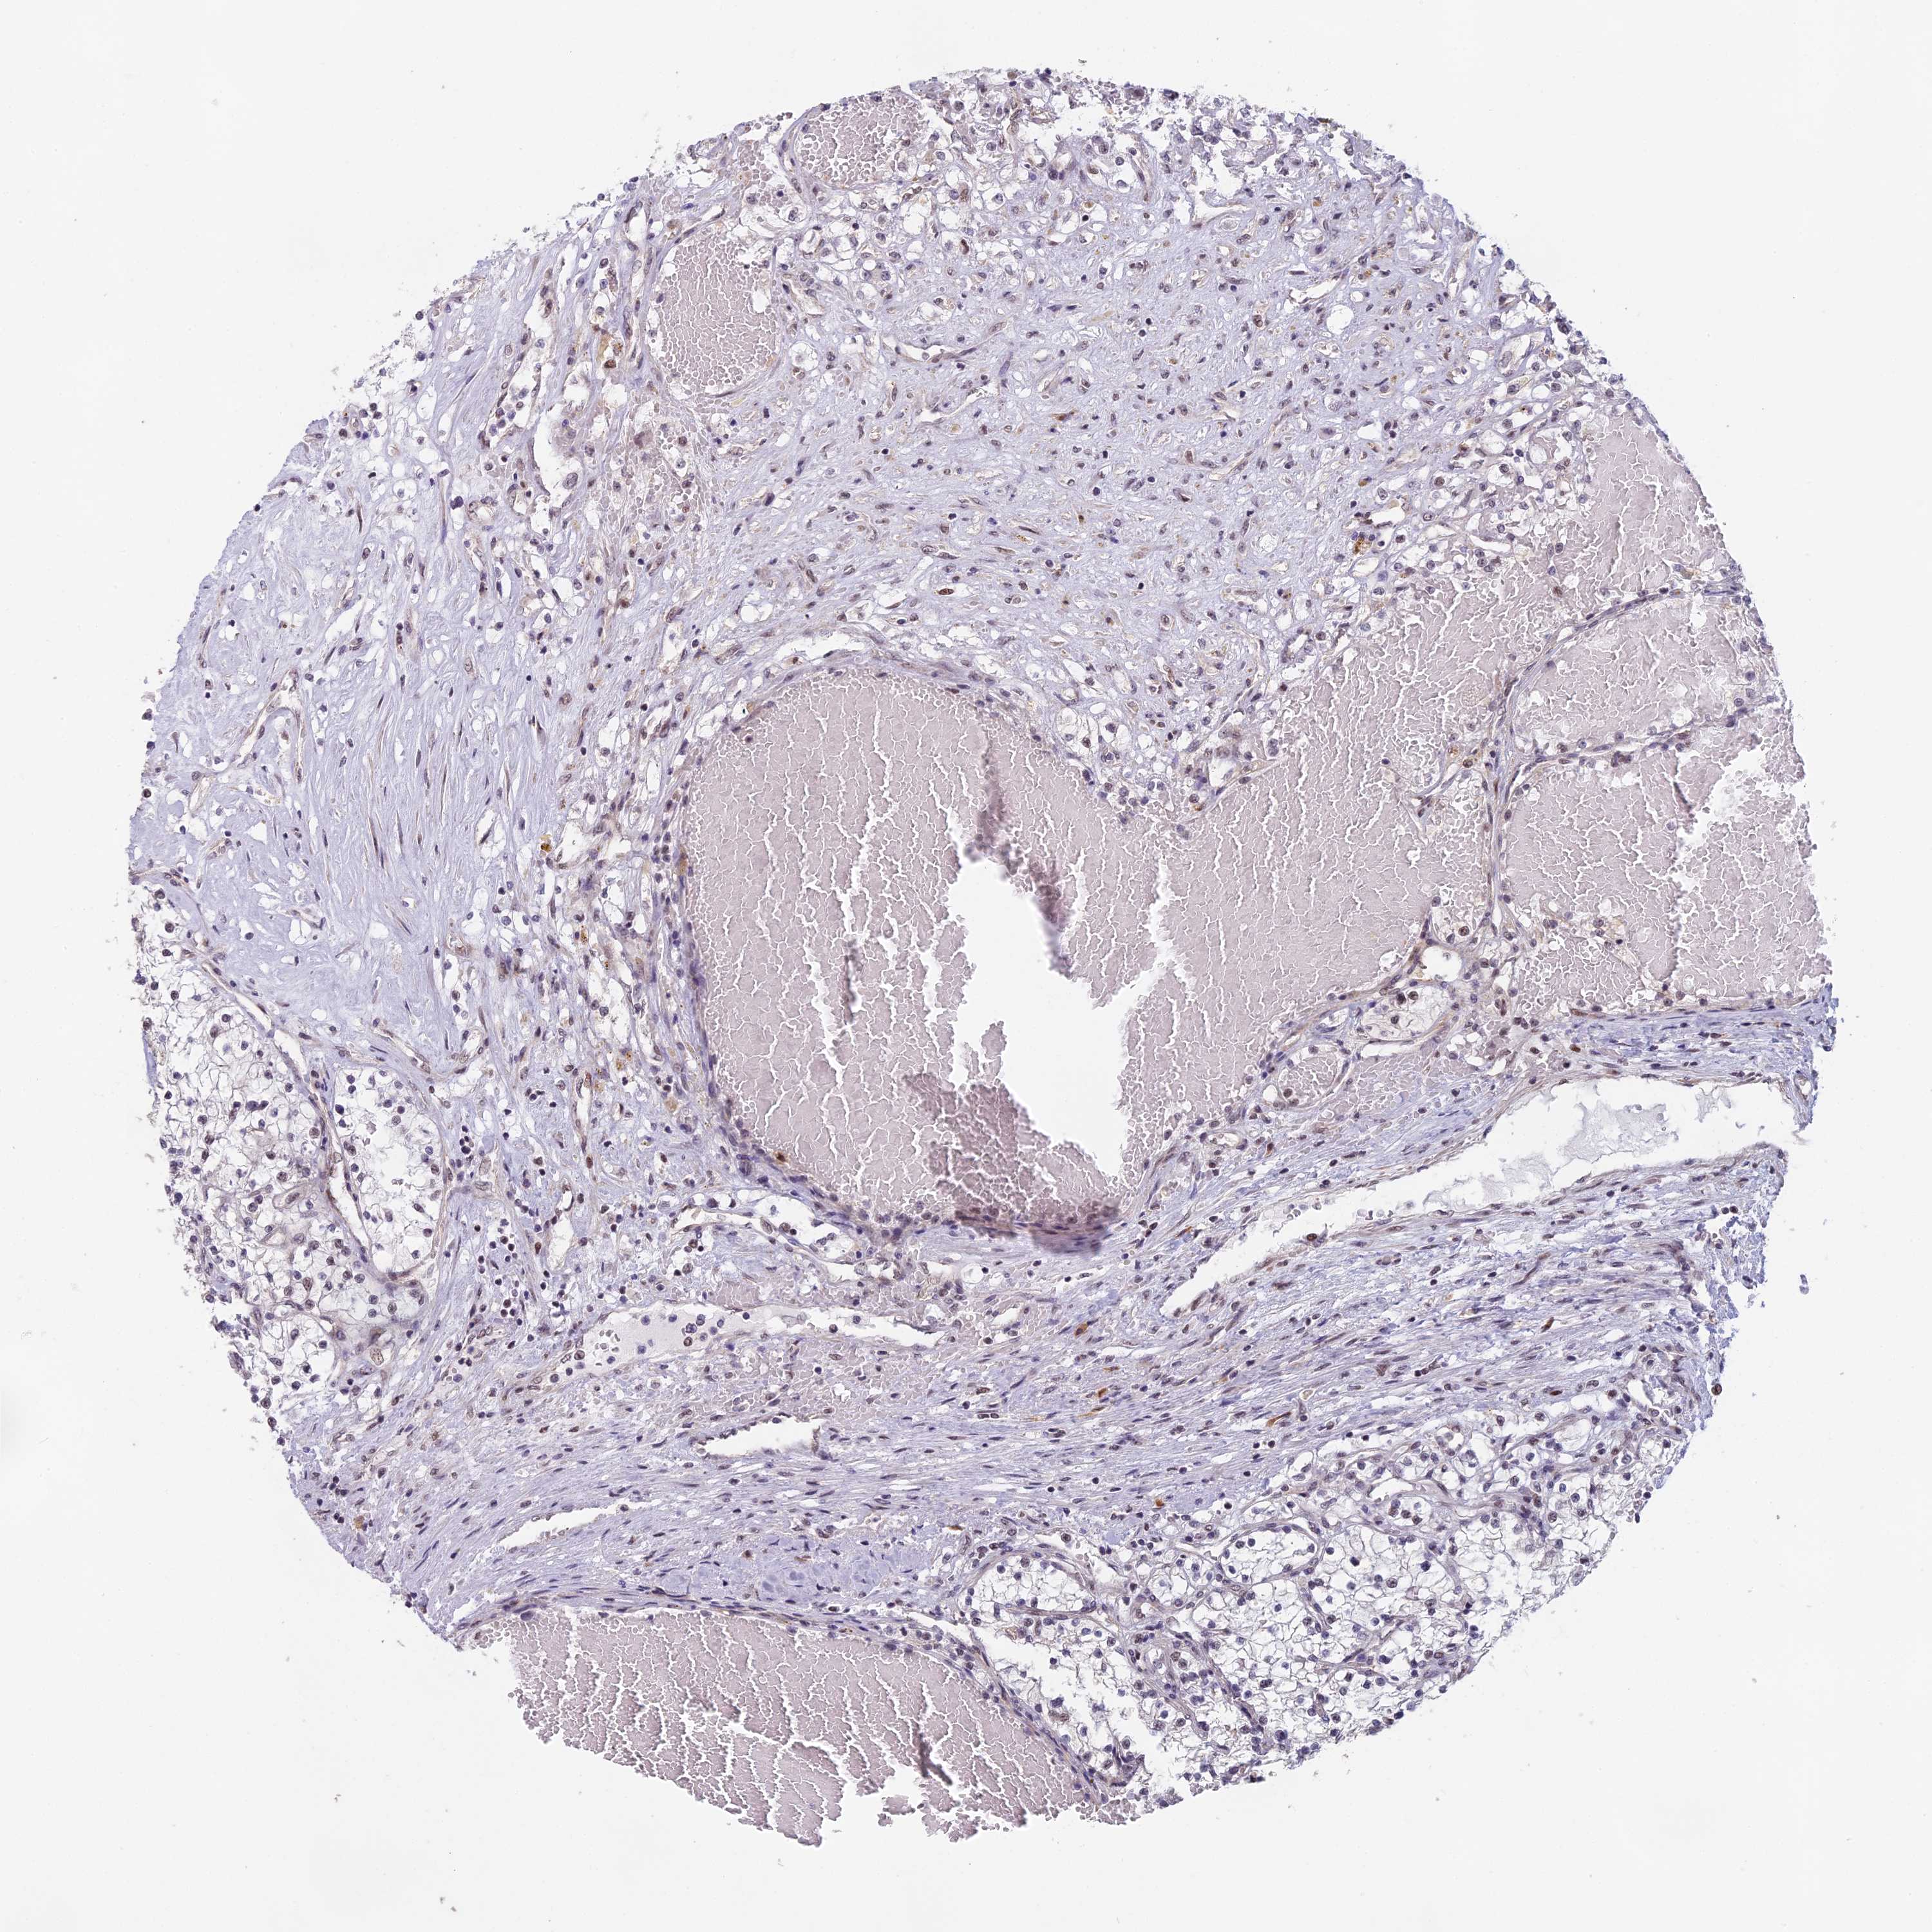

KIDNEY RENAL CLEAR CELL CARCINOMA (TCGA) - Interactive survival scatter ploti

The Survival Scatter plot shows the clinical status (i.e. dead or alive) for all individuals in the patient cohort, based on the same data that underlies the corresponding Kaplan-Meier plots. Patients that are alive at last time for follow-up are shown in blue and patients who have died during the study are shown in red.

The x-axis shows the expression levels (FPKM) of the investigated gene in the tumor tissue at the time of diagnosis. The y-axis shows the follow-up time after diagnosis (years). Both axes are complimented with kernel density curves demonstrating the data density over the axes. The top density plot shows the expression levels (FPKM) distribution among dead (red) and alive patients (blue). The right density plot shows the data density of the survived years of dead patients with high and low expression levels respectively, stratified using the cutoff indicated by the vertical dashed line through the Survival Scatter plot. This cutoff is automatically defined based on the FPKM cutoff that minimizes the p-score. The cutoff can be changed by dragging the vertical line or by entering a cutoff value in the square labeled "Current cut-off".

Under the Survival Scatter plot the p-score landscape (black curve; left axis) is shown together with dead median separation (red curve; right axis). Dead median separation is the difference in median mRNA expression between patients who have died with high and low expression, respectively. It is calculated as follows: median FPKM expression of dead patients with high expression - median FPKM expression of dead patients with low expression. This is intended to aid the user in visually exploring custom cutoffs and the associated p-scores and dead median separation.

Individual patient data is displayed and can be filtered by clicking on one or more of the category buttons on the top of the page. Categories describing expression level and patient information include: high, low, alive, dead, female, male and tumor stages. The scale of the x-axis can be toggled between linear and log-scale by clicking on the "x log" button. Mouse-over function shows TCGA ID, patient information and mRNA expression (FPKM) for each patient.

& Survival analysisi

Kaplan-Meier plots summarize results from analysis of correlation between mRNA expression level and patient survival. Patients were divided based on level of expression into one of the two groups "low" (under cut off) or "high" (over cut off). X-axis shows time for survival (years) and y-axis shows the probability of survival, where 1.0 corresponds to 100 percent.

MORF4L1 is validated prognostic, high expression is favorable in Kidney Renal Clear Cell Carcinoma (TCGA)

Best expression cut offi

Based on the FPKM value of each gene, patients were classified into two groups and association between prognosis (survival) and gene expression (FPKM) was examined. The best expression cut-off refers the FPKM value that yields maximal difference with regard to survival between the two groups at the lowest log-rank P-value. Best expression cut-off was selected based on survival analysis .

When clicking on this number, the vertical dashed line indicating cut-off, the interactive survival plot, and the Kaplan-Meier curve will be adjusted to show results based on the best expression cut-off.

: 181.68

Average pTPM 281.0

Number of samples 521